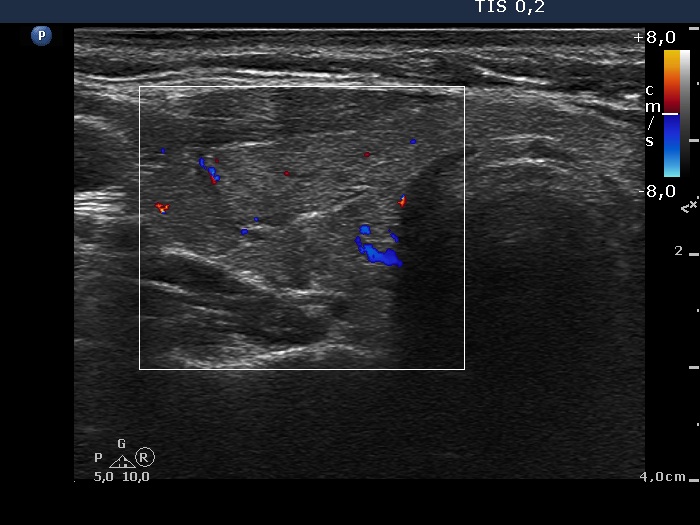

Ultrasonography: The thyroid was minimally-moderately hypoechogenic and presented fibrosis. There was a cystic lesion in the lower dorsal part of the right thyroid bed.

Further laboratory tests aTPO 308 U/mL, calcium 2.25 mM/L, phosphorus 1.11 mM/L, parathormone 40.9 pg/mL (normal range: 10-65). The parathormone content of the cystic fluid was 383 pg/mL.

Final diagnosis: Hashimoto's thyroiditis in euthyroid state. Parathyroid cystadenoma.